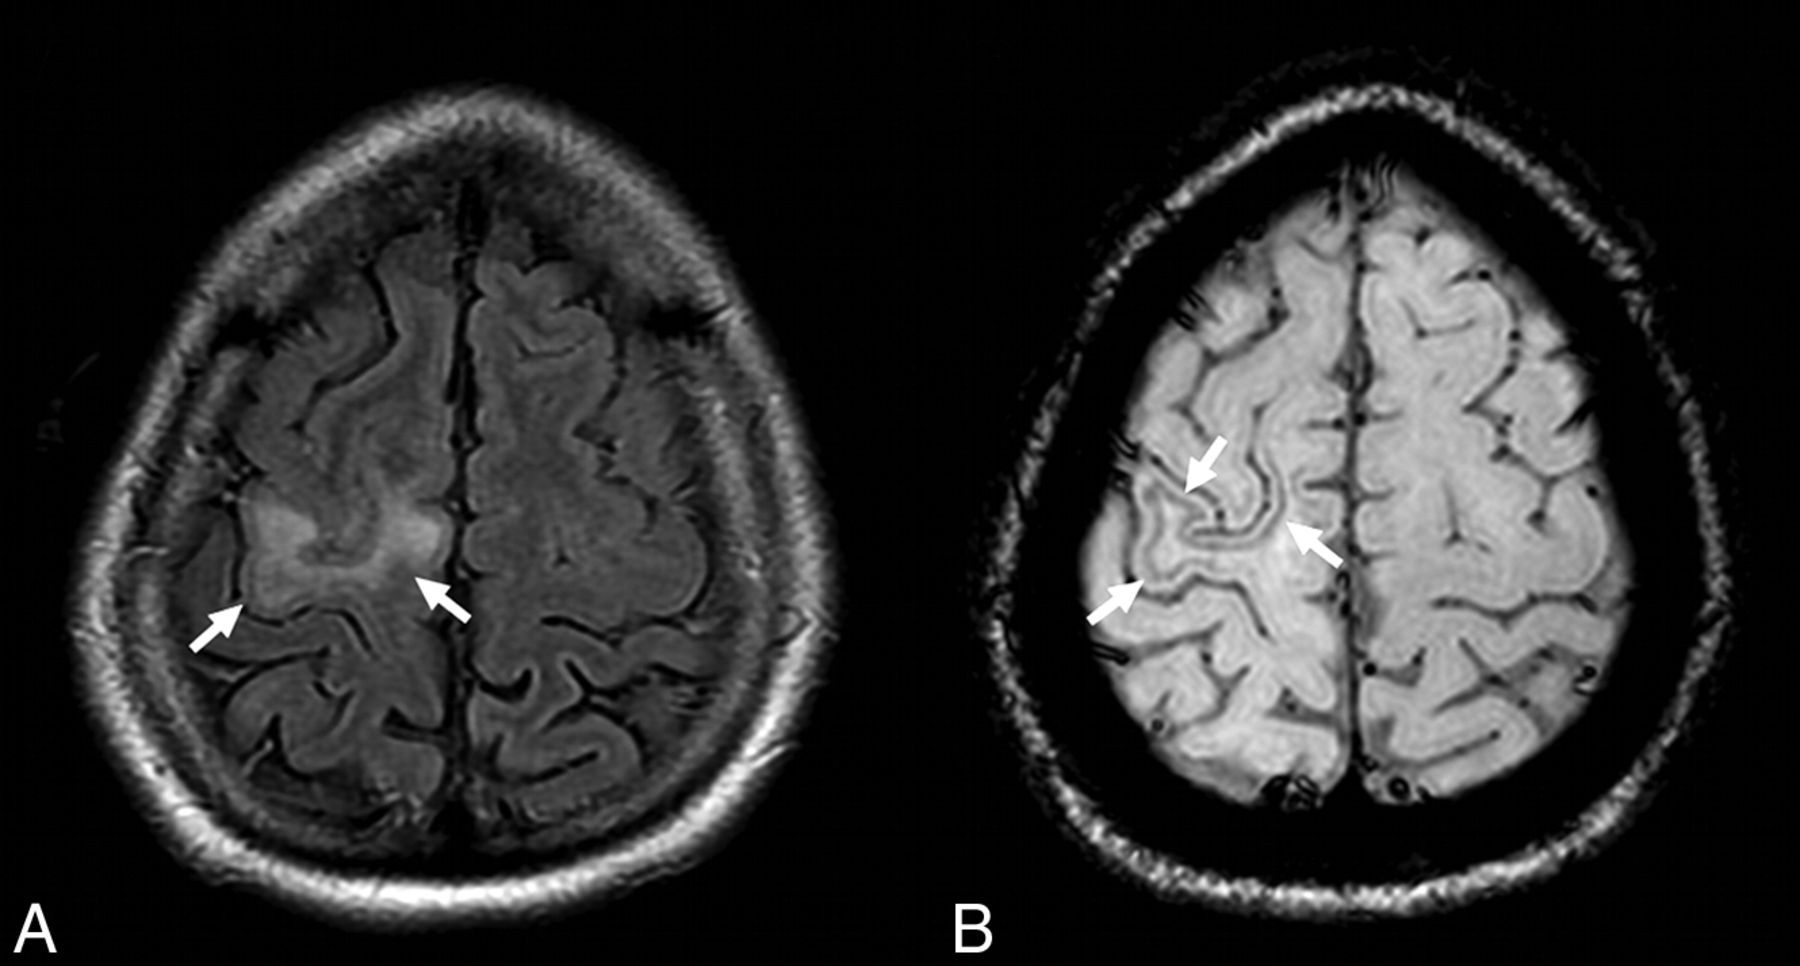

In patient 11 at the symptomatic stage, the NTZ-PML lesion appears hyperintense on the FLAIR image involving the right precentral gyrus (A, arrows). The SWI sequence reveals a hypointense rim involving the U-fibers adjacent to the PML lesion (B, arrows).

Longitudinal changes were observed in 8 patients (9 PML lesions), with cortical T2* and/or SWI low signal intensity appearing or becoming more prominent.

Cortical or U-fiber T2* hypointensity was systematically adjacent to a PML lesion, hyperintense on FLAIR images. However, only a faint FLAIR hyperintensity was visible adjacent to the area of cortical T2* hypointensity for 3 MR imaging examinations: 2 performed at the symptomatic stage in patient 7 and 1 performed at the asymptomatic stage in patient 12 (Figs 3 and 4, respectively).